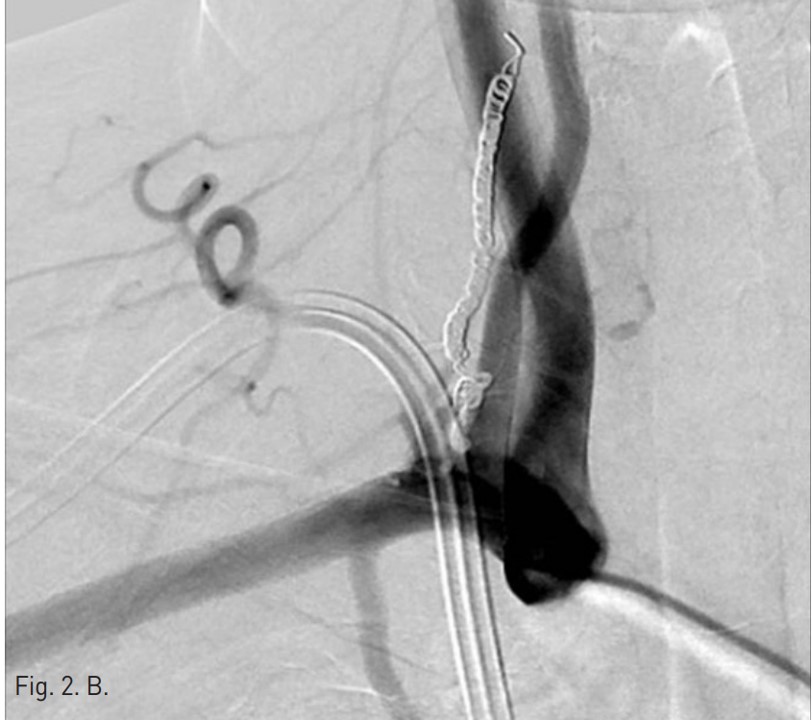

Permanent catheter insertion 이후 일주일 뒤 시행한 혈관조영술에서 갑상목동맥(right thyrocervical trunk)의 branch에 작은 거짓동맥류(small pseudoaneurysm)가 있고 permanent catheter를 insertion하는 과정에서 비롯된 합병증으로 판단되었음(Fig. 1A,B). 따라서 갑상목동맥의 기시부에서부터 아래 갑상동맥(inferior thyroidal artery)의 기시부까지 색전술을 시행하기로 함. Microcoil 및 glue를 사용하여 embolization 시행 후 조영제 검사에서 거짓동맥류는 보이지 않고(Fig. 2A,B) 임상 소견도 모두 호전되었음.

아래갑상동맥의 원위부의 색전을 방지하기 위해서 한 개의 coil(F-IDC 2D 3x6cm, Boston scientific)이 사용되었고 아래갑상동맥의 기시부에 색전술을 시행하였음. 그 후에 아홉 개의 microcoil(Tornado microcoil, Cook)과 one vial의 glue(Histoacryl 0.5cc)를 이용하여 아래갑상동맥과 갑상목동맥에 색전술을 시행함.

색전술 후 혈관조영에서 오른쪽 갑상목동맥은 성공적으로 색전이 되었고 더 이상 거짓동맥류는 보이지 않았음(Fig. 2A,B).

Fig. 2. B

Fig. 2. On post-embolization angiography, the right thyrocervical trunk was successfully embolized and the pseudoaneurysm was not visualized. The embolization was done using nine of microcoils and one vial of glue(arrow head).